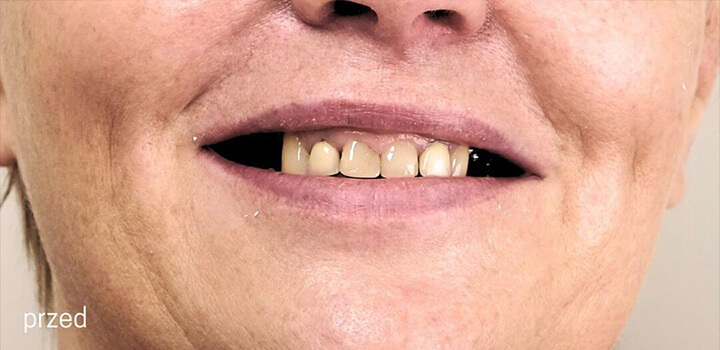

Efekty, które mówią same za siebie